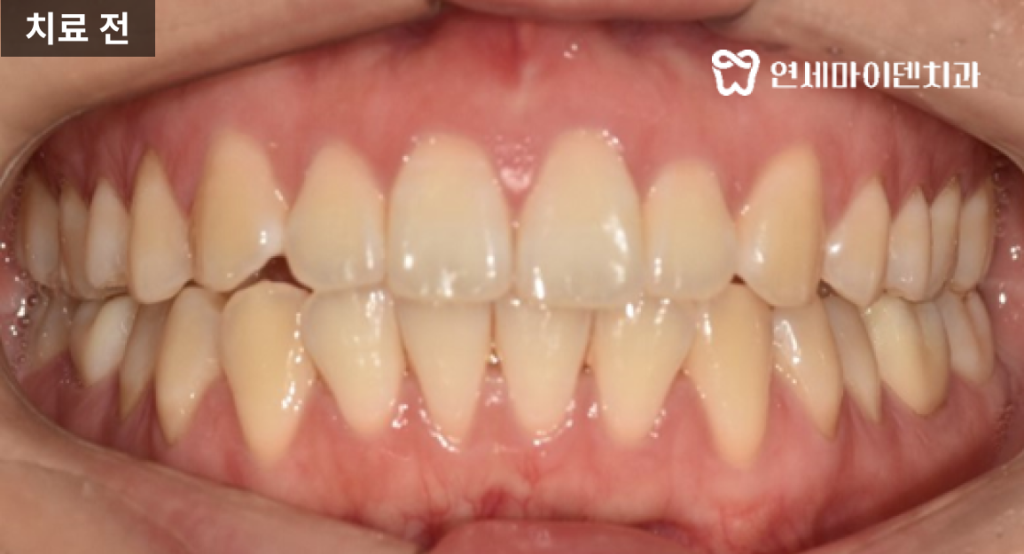

정면 사진에서는 중심선이 우측으로 틀어진 안면 비대칭이 관찰되었으며,

이런 환자분의 상태를 꼼꼼히 확인해서 치료 계획을 크게 2가지로 나누었습니다.

치료 계획은 크게 두 가지 방향으로 나뉘었습니다.

- 기존 레진 및 높게 제작된 크라운 제거

→ 원래의 교합 상태로 회복시켜 과도한 높이를 조정하였습니다. - 치아의 전체적인 후방 이동 및 중심선 교정

→ 비대칭을 해소하고 입술 돌출을 줄이기 위한 방향으로 설정하였습니다.